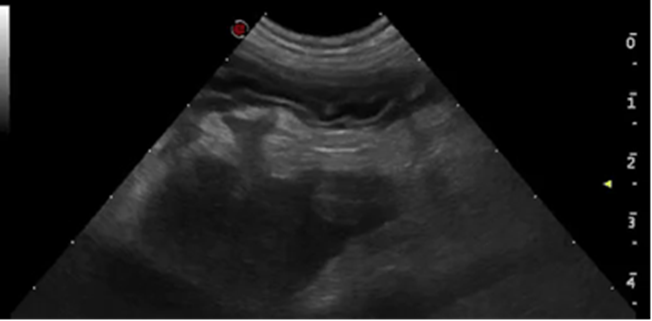

An advanced, highly practical ultrasound course designed to extend diagnostic capability, combining hands-on training in challenging abdominal structures, Doppler techniques and ultrasound-guided sampling for confident clinical application.

This course is suitable for you if you‘re a general practitioner who already has experience performing an abdominal ultrasound and would like to elevate your skills in evaluating the more challenging abdominal structures and at performing ultrasound-guided sampling. You’ll also learn how to use ultrasound for the assessment of the thorax (except heart) and neck, increasing the range of applications of this imaging modality that you can offer your patients. This two day Advanced Small Animal Ultrasound course will consist of a combination of lectures and several hands on practical sessions with the guidance of the course tutors.

- Become more proficient at identifying adrenal glands and pancreas, familiarising yourself with the different anatomical landmarks used to find these small organs and being able to differentiate normal appearance from pathological changes

- Gain improved confidence on evaluating difficult areas like the pylorus and urinary bladder trigone